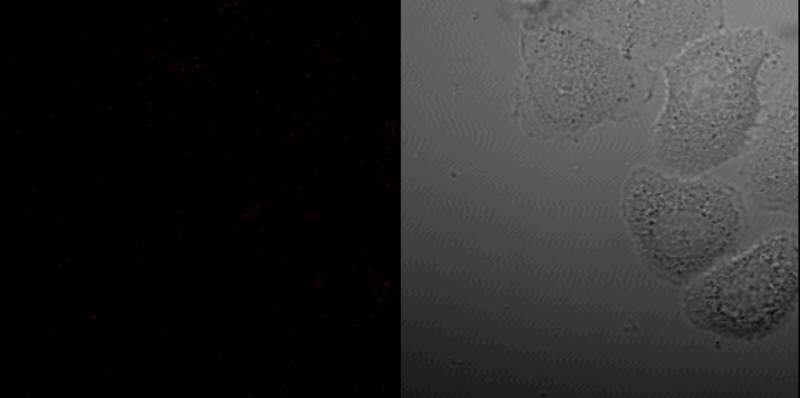

HepG2ϸ°ûÖÐÕâ¸ö¸í¸í´ñ´ñµÄСµãÊÇʲô£¿ ÒÑÓÐ1È˲ÎÓë